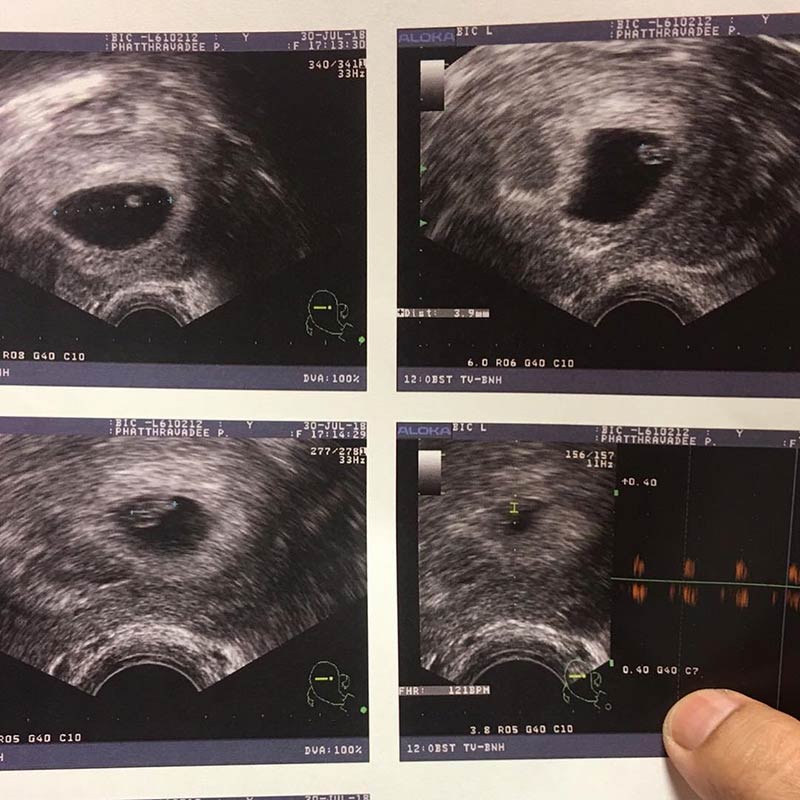

หลังจากที่หนูเล็ก ก่อนบ่าย โพสต์ข้อความให้เห็นถึงข่าวดี ว่าตอนนี้ตนเองกำลังจะมีลูกน้อยแล้ว ก็ทำให้ทั้งครอบครัวปลื้มปริ่ม ดีใจ และมีความสุขกันถ้วนหน้า ทว่า เส้นทางของคนเป็นแม่ไม่ง่าย โดยเฉพาะกับหนูเล็กที่เจอบททดสอบตั้งแต่วันแรกเลยทีเดียว

ทั้งนี้ เมื่อวันที่ 2 สิงหาคม 2561 หนูเล็กได้ออกมาเผยความลำบากของการเป็นแม่ว่า ตอนนี้ตนเองแพ้ท้องหนักมาก ได้แต่สับสนว่าทำไมมันหนักขนาดนี้ เพราะหลังจากอาเจียนแล้วก็อาเจียนอีก เวียนหัวแค่เปลี่ยนมุมเท่านั้น